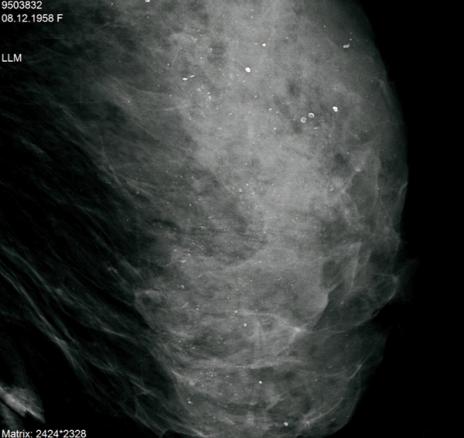

© Sylvie Lemery - La Revue du Praticien Agrandi du profil gauche. Microcalcifications diffuses et bilaterales, non evolutives. BIRADS 2.